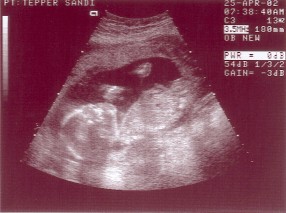

20 Weeks Pregnant - April 25, 2002

Emma at 19 wk 4 days Well, that's her. I know these things are difficult to see so I'll just tell you - she's laying on her side with her head to the left and bottom to the right. If you look at her head you can see the profile of her sweet little face!

The whitish smear above her face is her hand. You can make out her spine and sternum - think what rib connection would look like and you'll pick them out! The elongated blob coming up and to the left from her bottom end is her leg - if you look closely you can see her femur (very white line). And the blob above the end of that is her other knee - believe it or not! And, yes it is connected to the other leg-bone!